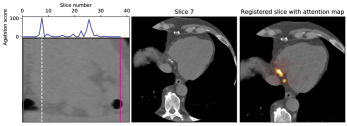

V-C Decision feedback

Decision feedback visualizes attention of the calcium scoring ConvNet. This feedback informs and end-user about the regions that contributed to the calcium score. Figure 7 shows examples of such feedback. The feedback helps an expert to quickly navigate and evaluate the image slices containing CAC.

We propose visual feedback as an optional qualitative tool, but we have performed a quantitative analysis to provide insight in its accuracy. To obtain quantitative results we analyzed heatmaps for slices with predicted calcium scores. The heatmaps were warped to the original image spaces by using the inverse transformation matrices. The values of the heatmaps were scaled between 0 and 1 to mimic probability maps for CAC candidate voxels. CAC candidates were defined as high density 26-connected voxels with a volume between 1.5 and 1,500 mm3[19]. For evaluation of these maps we performed precision-recall analysis (Figure 8). We have defined an optimal threshold by selecting the maximum F1 (i.e. Dice) score on the validation set. Table IV shows the obtained scores using the selected threshold on the test sets. The results show that detection performance is very accurate on the validation set as well as the test set.

Additionally, decision feedback aided our analysis by clarifying incorrect calcium scores. Decision feedback revealed that the largest CVD miscategorizations were not caused by incorrect quantification but by incorrect recognition of CAC. Figure 9 shows six examples of the largest miscategorizations made by the calcium scoring ConvNet. The majority of errors were made in identification of calcifications near the coronary artery ostia. Calcifications near the ostia can be partly in the aorta and partly in the coronary artery. These calcifications are difficult to distinguish, especially when no information of neighboring slices is available.